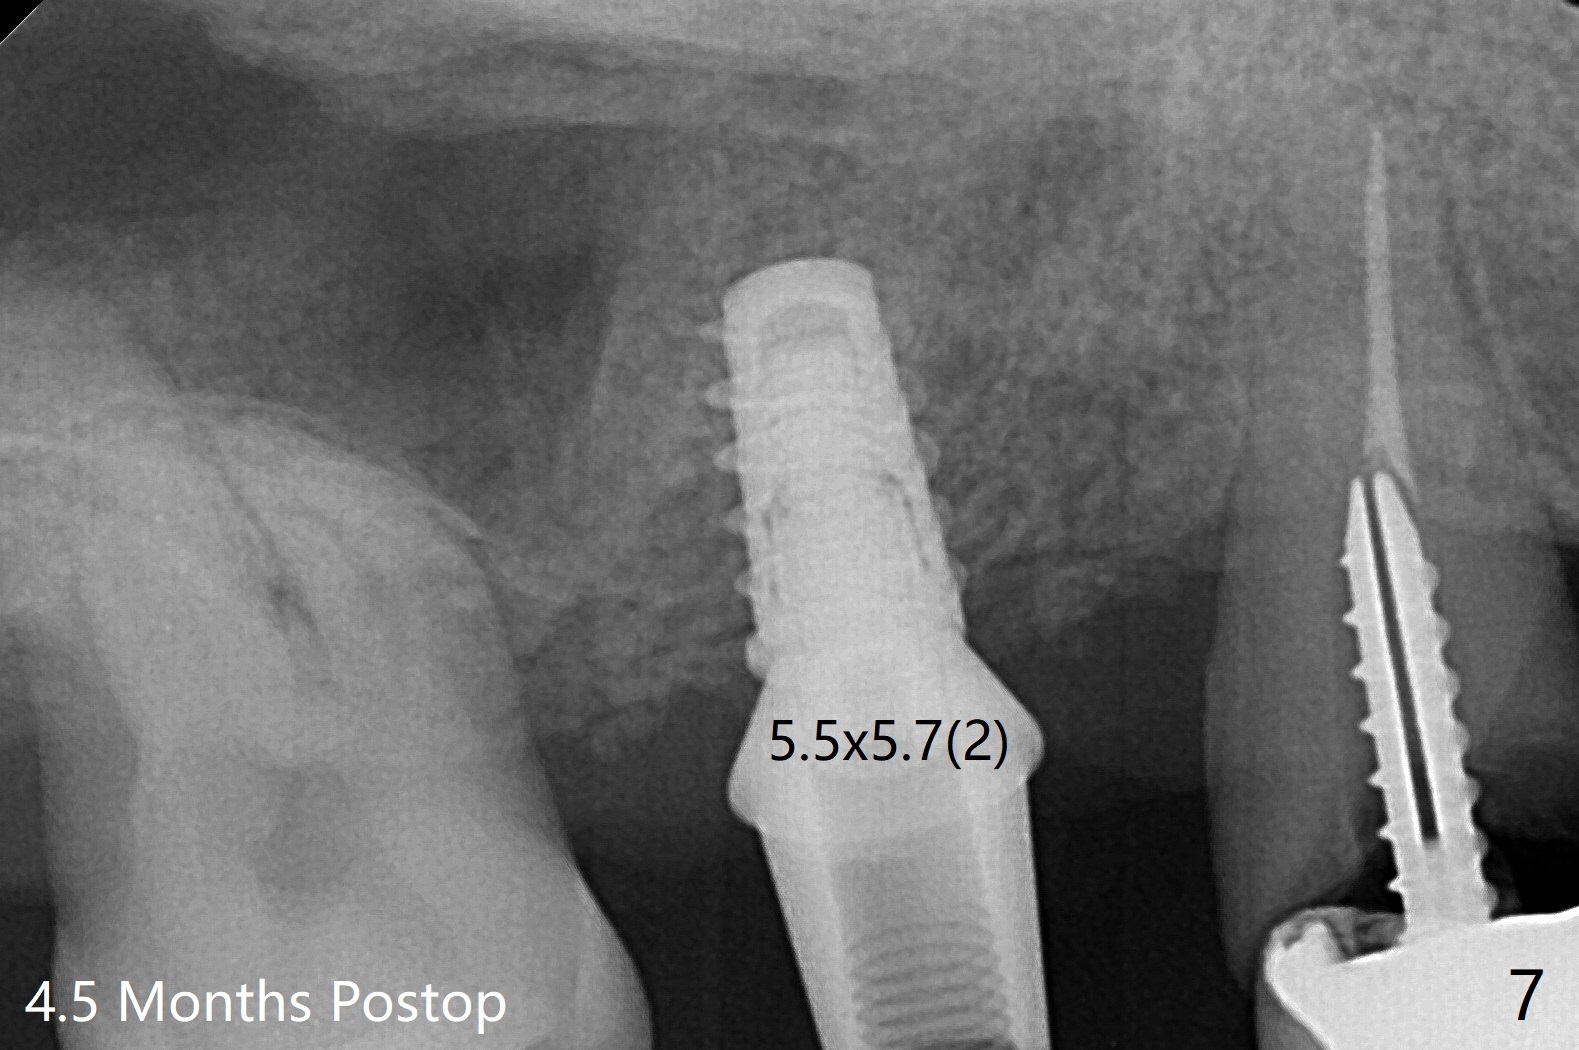

智齿第二磨牙即种

树脂敷料稳定性因素:前后有无邻牙,下面有无基台,基台长短

下颌即种: 树脂敷料重要性